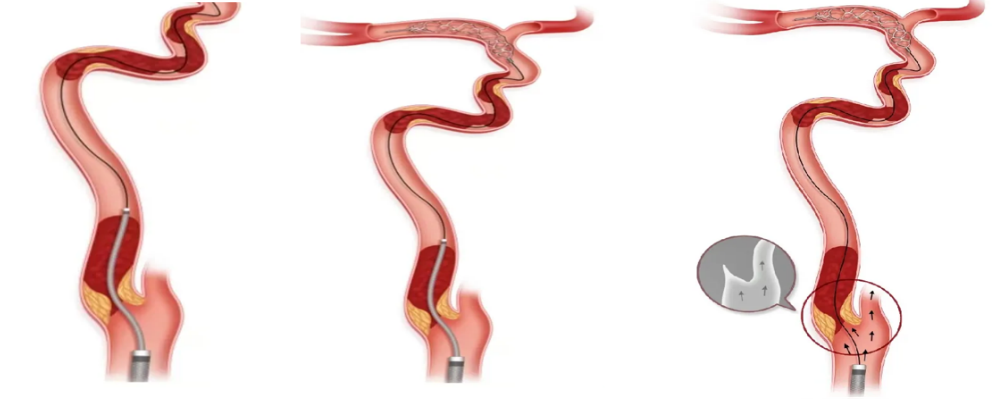

附: 球囊辅助穿梭技术(BAT)

颅内动脉原位狭窄(ICAD)基础上大血管闭塞,常见的取栓策略包括:导管抽吸、支架取栓或直接血管成型等。ICAD机械取栓的特点在于血栓负荷量小,但遇到血栓负荷量大的案例,最快捷的开通方式可能在于吸栓导管越过狭窄直接抽吸。

但是,抽吸导管如何越过狭窄?

传统的方法如,先ICAD血管成型,然后让导管越过狭窄;但缺点在于,ICAD狭窄改善后,前向血流恢复,容易导致原有血栓向远端逃逸,导致新流域梗死。

其技术核心在于:球囊“半含”,即球囊一半隐藏于抽吸导管内,另外一半露出抽吸导管外、位于狭窄处,然后充盈球囊。部分泄压的同时在球囊辅助下将导管越过狭窄进行抽吸。

其目的在于:① ICAD狭窄血管成型;② 借助充盈球囊,减少大口径抽吸导管与微导丝的缝隙,降低壁架效应“ledge effect”,形成无缝隙载体向前推送,使抽吸导管顺利越过狭窄,到达远端直接抽吸。

BAT技术:5-6F 125抽吸导管,半含2*15mm球囊,3atm压力充盈下,顺利将抽吸导管通过狭窄段。

球囊辅助穿梭技术(BAT)的潜在优势在于:开通快速、节省取栓支架费用、以及抽吸导管在狭窄处阻断血流,预防栓塞等。